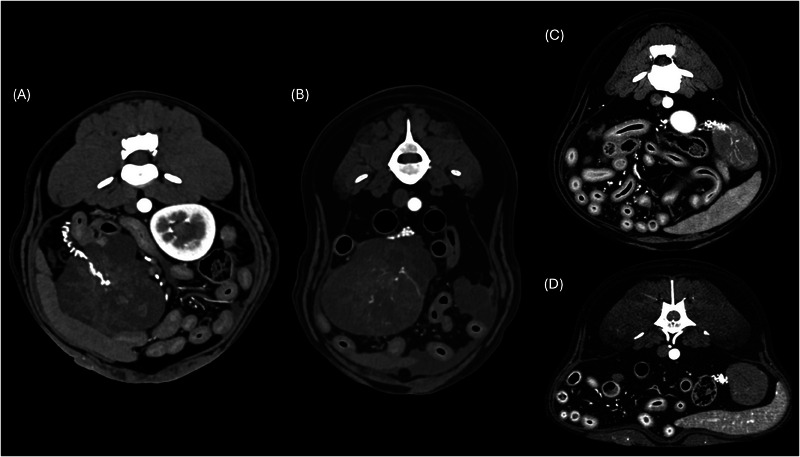

The aim of this retrospective multicentric case series is to describe the CT findings of ovarian neoplasia in dogs. Twenty dogs with pre- and postcontrast CT exams and cytological/histological diagnosis of ovarian neoplasia were included. Five dogs presented with bilateral tumors, for a total of 25 neoplasms: 15 carcinomas (4 bilateral), 4 granulosa cell tumors, 2 poorly differentiated malignant neoplasia (bilateral), 2 luteomas, 1 teratoma, 1 dysgerminoma. In two dogs, the tumor developed from an ovarian remnant. Ovarian tumors showed variable size, lobulated shape, and precontrast heterogenous appearance. Mineral foci and/or fat components were rare, observed in teratoma, granulosa cell tumors (2), and ovarian carcinoma. Tumor type was not found to be associated with any CT features. Larger masses were more likely located in the central abdomen ventral to the ipsilateral kidney, demonstrated signs of tumor rupture, and were associated with abdominal or sternal lymphadenopathy and peritoneal effusion. A tortuous ovarian artery was constantly detectable, associated with an enlarged gonadal vein (12 cases). Related cavitary changes were peritoneal effusion (14 dogs) and sternal lymphadenopathy (7 dogs). Presumed or confirmed metastasis was reported in 9 of 20 cases, with CT evidence of transcoelomic (serosal thickening, peritoneal nodules, omental cake, implant lesions to the liver, spleen, and diaphragm), lymphatic and hematogenous spread (lungs, liver, bone, muscles, and spleen). In conclusion, the present study reports the CT features of different canine ovarian neoplasia. A tortuous ovarian artery may be useful to consistently recognize the ovarian origin of a large abdominal mass.